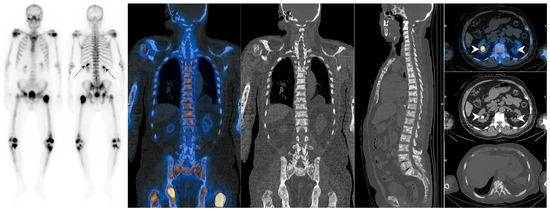

7.1. Metastatic Superscan

7.1.1. Superscan Pattern in Patients with Prostate Cancer

7.1.2. Dynamic Changes in Prostate Cancer Patients with Superscan

7.2. Metabolic Superscan

7.3. Distinguishing Metabolic Superscan from Metastatic Superscan